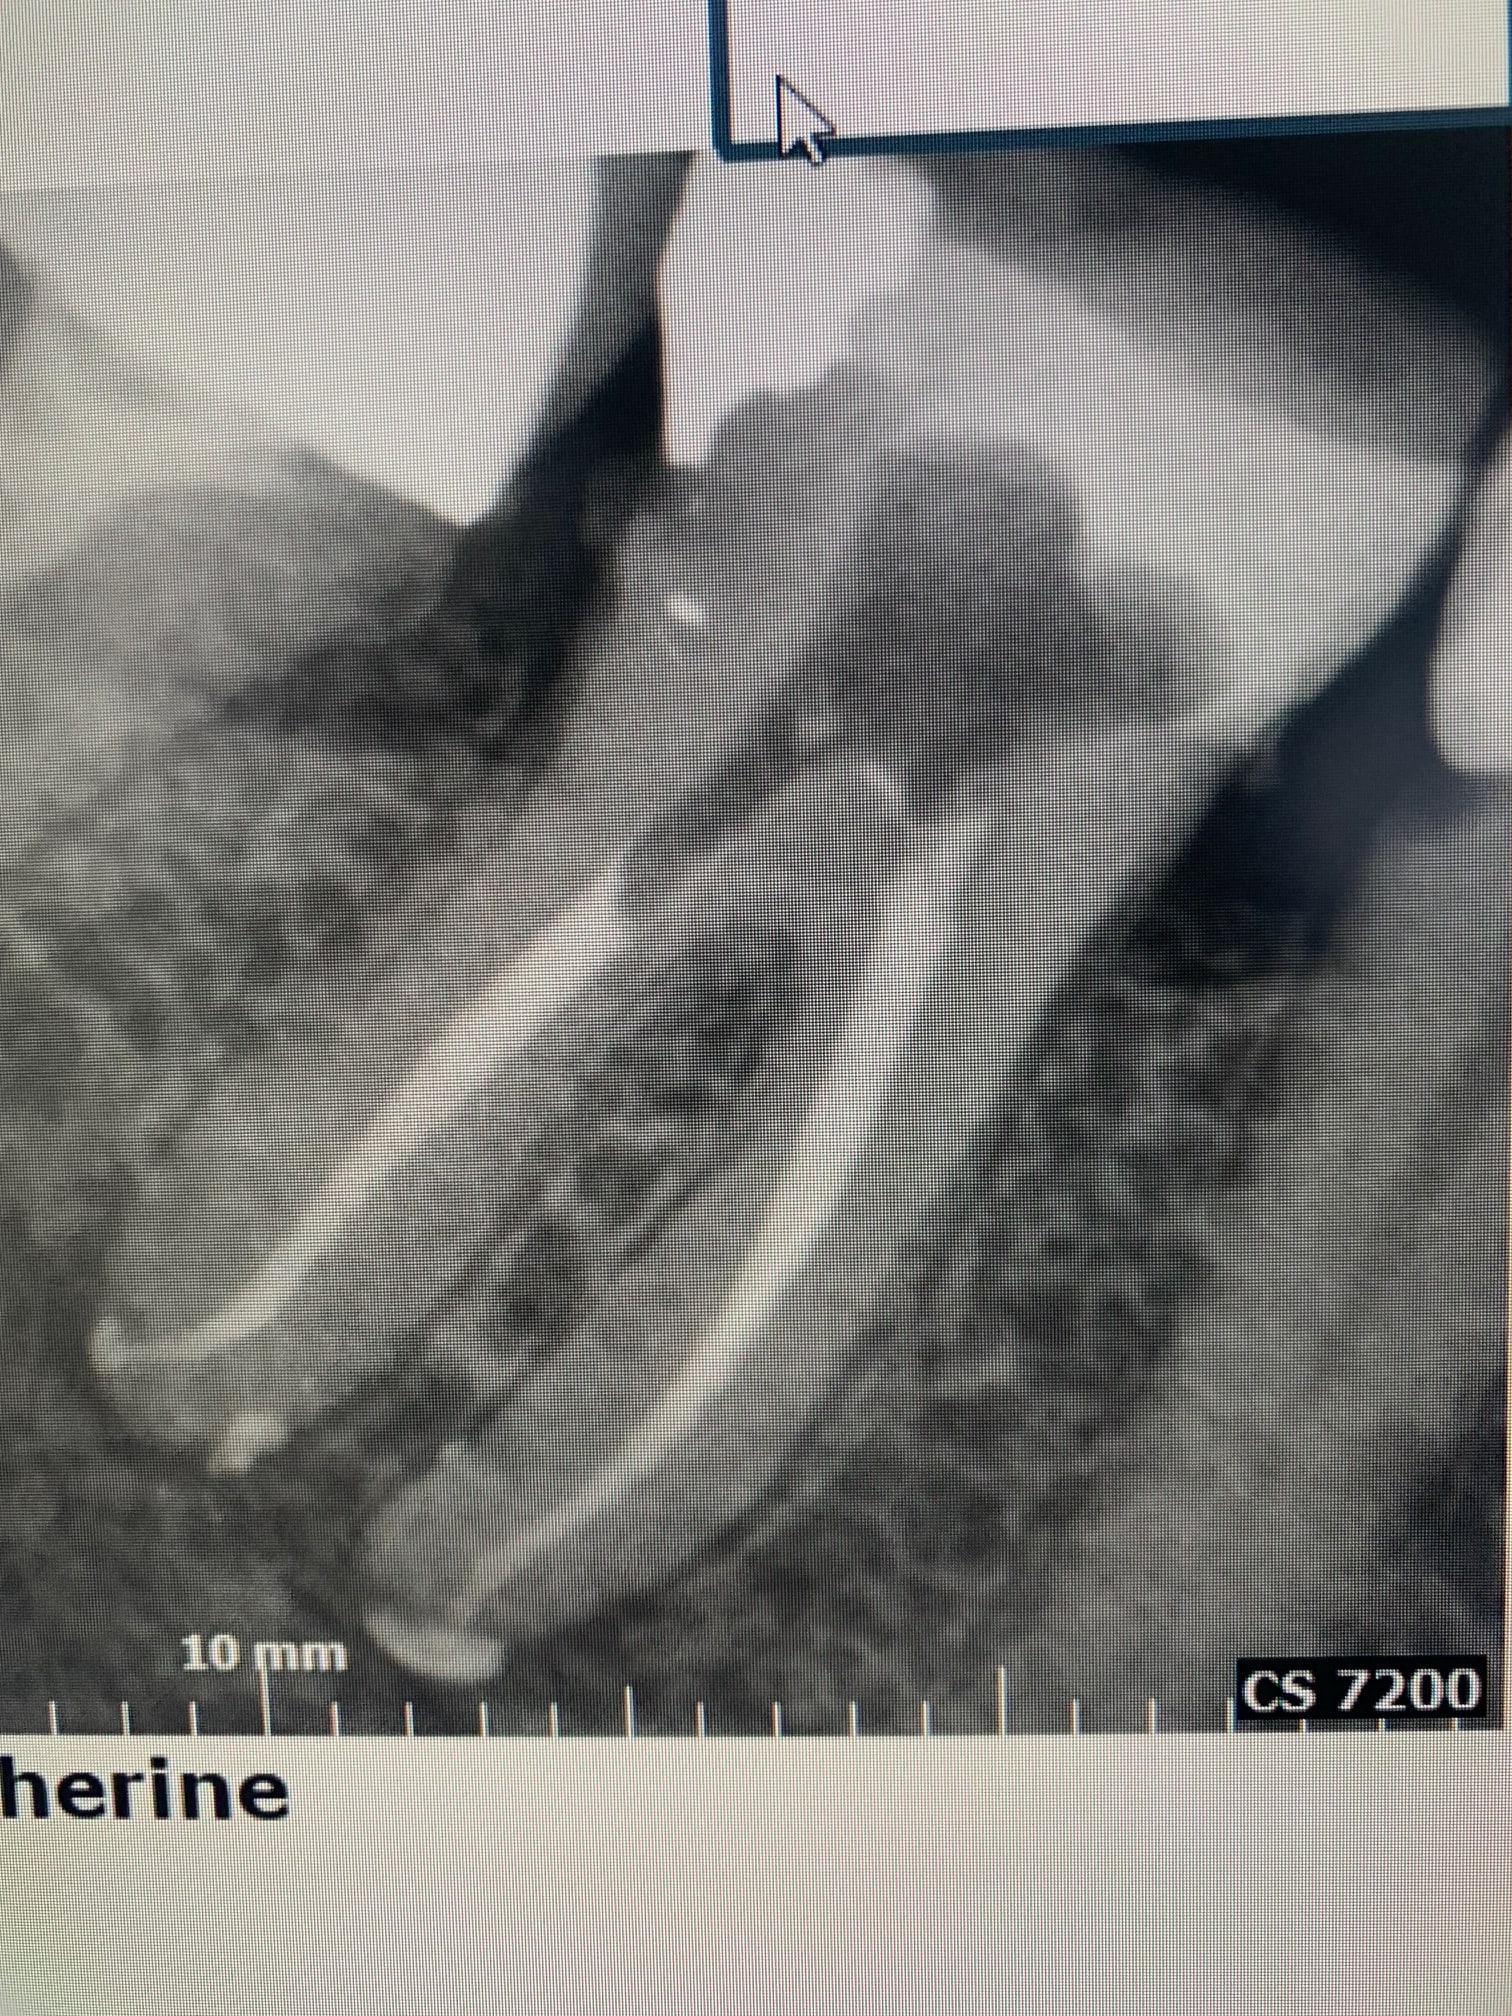

Mais en lingual de la racine mésiale d’une 46.

Cbct

La patiente était en pulpite. Son praticien a passé 2 fois une heure dessus. Il a cassé deux instruments, n’a jamais réussi à anesthésier et m’a adressé en l’état.

J’ai eu une rétro par mail qui n’apportait rien de plus. Bien entendu j’ai pensé à une fistule mais la dent était en pulpite il y a peu…

Le NDI passe bien dans ce qu’on voit et finit bien par un trou mentonnier vestibulaire…

Une émergence linguale est possible avec un dédoublement.

Claeys & Wackens (2005) ont rapporté un cas de canal mandibulaire double dont l’origine était constituée par un foramen

mandibulaire double. Le plus haut des deux canaux présentait une direction linguale avec un orifice antérieur (foramen mentonnier lingual!).

Comme CT et Enlaye: si le nerf passe dedans, c'est surement un foramen atypique.

Moritooth j’ai eu une rétro qui ne me donnait pas assez d’info, j’ai donc réalisé un cbct 5x4 en 100 microns, le praticien ayant rendu le cas bien complexe avec ses 2 instruments fracturés.

CT a très vraisemblablement donné la bonne réponse. Merci. Je n’avais jamais vu ce type de configuration.